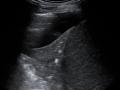

Figura 1 - Radiografia de tórax, evidenciando área de consolidação no lobo superior esquerdo, associada à imagem radiolucente, de configuração nodular. Outra imagem radioluscente de configuração nodular e halo denso é visibilizada no lobo inferior esquerdo.